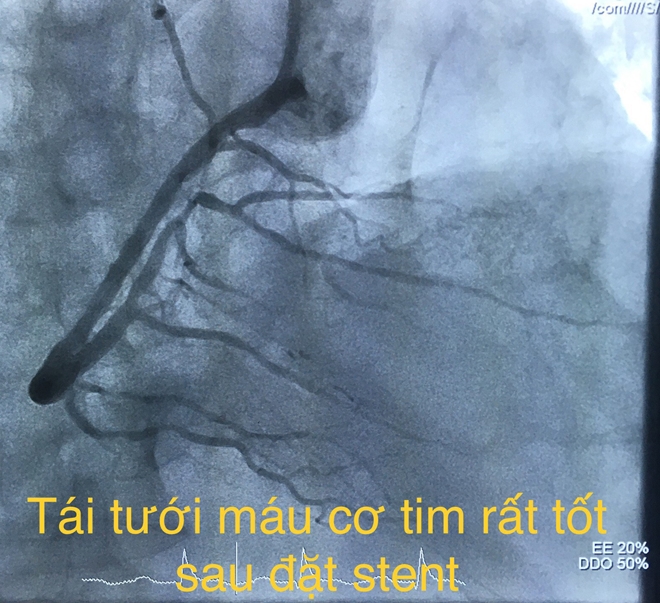

Các bác sĩ tiến hành dùng bóng nong động mạch vành phải và đặt một stent phủ thuốc. Thời gian tái thông mạch vành 20 phút.

Sau can thiệp tái thông, huyết động của bệnh nhân cải thiện rõ, sinh tồn ổn định và được đưa về Khoa Hồi sức tích cực – Chống độc để theo dõi và hồi sức nội khoa. Hiện bệnh nhân tỉnh, tiếp xúc tốt, dấu hiệu sinh tồn ổn định.

Bác sĩ xử trí hút huyết khối và can thiệp đặt stent tái thông mạch vành phải trong 45 phút. Sau can thiệp tái thông mạch vành, tình trạng bệnh tiến triển tốt, hết đau ngực, huyết động ổn định.